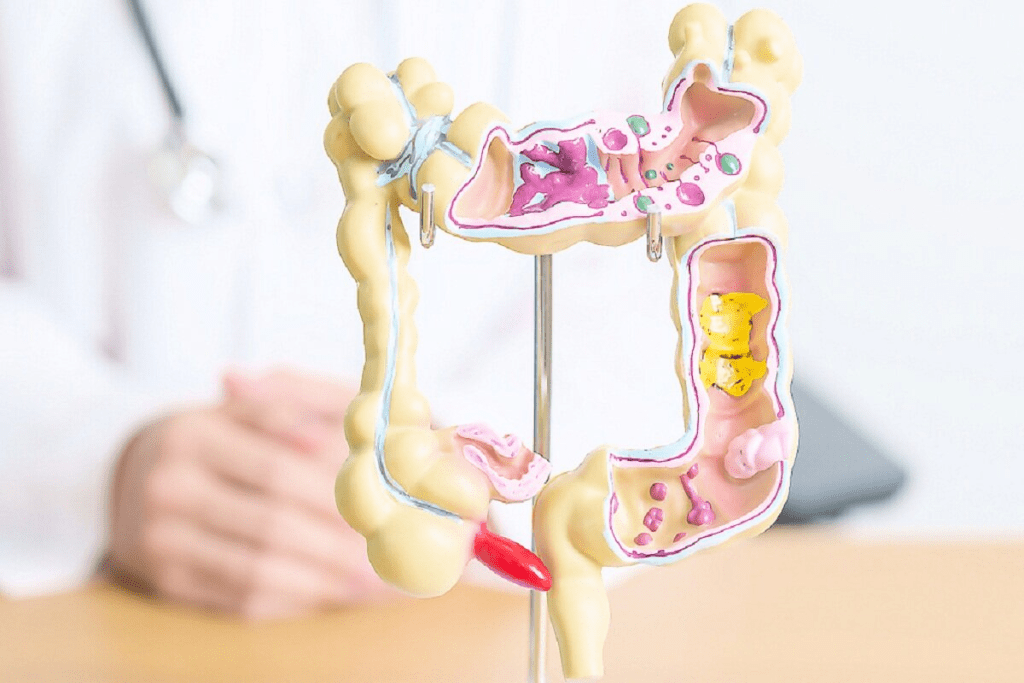

Anatomy of the Colon: How Long is the Colon and Its Structure

The colon is a key part of our digestive system. It’s about 5 feet long and has different parts. Each part has a special role in digestion and can be at risk for cancer.

The Length and Parts of the Adult Colon

The colon, or large intestine, is divided into sections. These include the cecum, ascending colon, transverse colon, descending colon, and sigmoid colon. Each section has its own job and can face different health issues, like cancer.

How Colon Structure Affects Cancer Development

The colon’s structure is key in understanding colon cancer. Different parts of the colon face different cancer risks. For example, the sigmoid colon is more prone to cancer because it’s exposed to more waste.

Knowing the colon’s anatomy helps us spot risk factors and create better screening plans. The colon’s length and structure affect its function and cancer risk.

Benign vs. Malignant Growths in the Colon

Growth in the colon can worry people, but not all are cancerous. Knowing the difference between benign and malignant growths is key for the right treatment.

Types of Non-Cancerous Masses

Benign growths in the colon come in different types. These include:

- Hyperplastic polyps: Small, usually harmless growths.

- Adenomatous polyps: Often benign but can turn malignant over time.

- Juvenile polyps: Common in kids, mostly benign.

It’s important to watch these growths. Some might turn into cancer.

Benign Tumors in the Large Intestine

Benign tumors in the large intestine can cause pain, bleeding, or bowel changes. Common types are:

- Lipomas: Fatty tumors that are usually harmless.

- Leiomyomas: Smooth muscle tumors that are typically benign.

Though not cancerous, these tumors can cause problems if they grow too big.

When to Be Concerned About Colon Growths

Not all colon growths need urgent attention. But, some signs can mean a higher risk of cancer. These include:

- Large size

- Irregular shape or surface

- Presence of symptoms like bleeding or pain

A healthcare provider can check these signs and suggest the right steps.